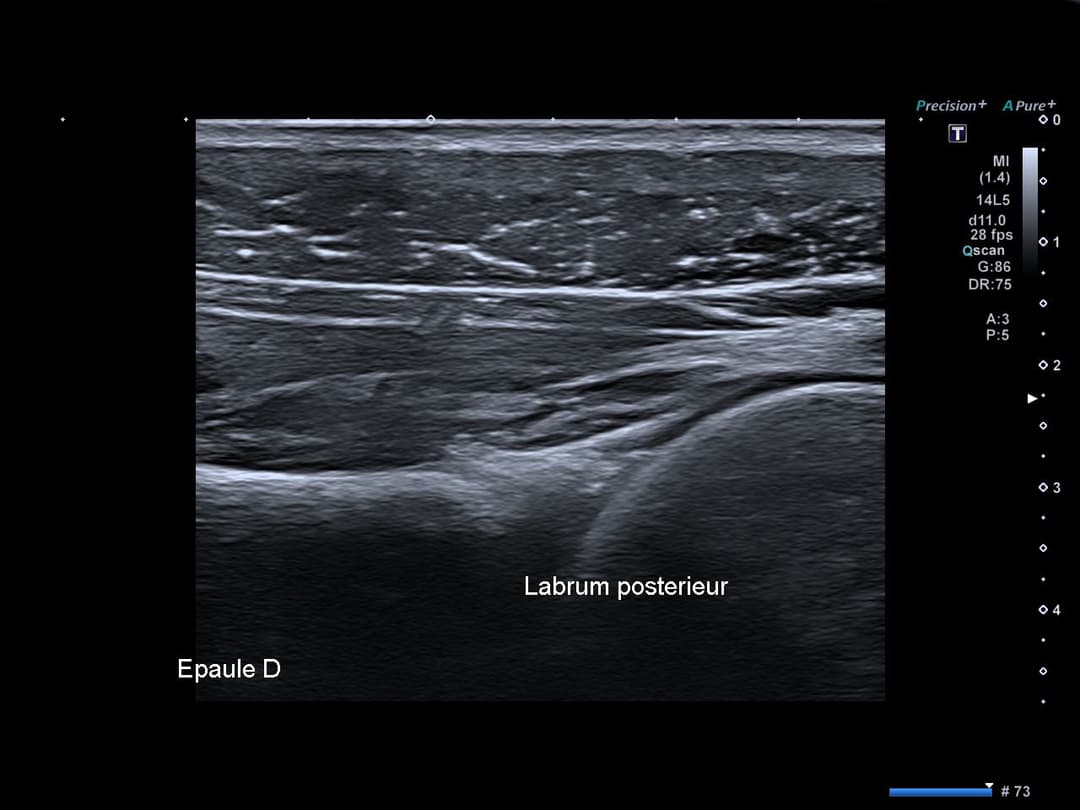

Recessus posterieur libre d'épanchement avec respect des rapports articulaires glénohuméraux